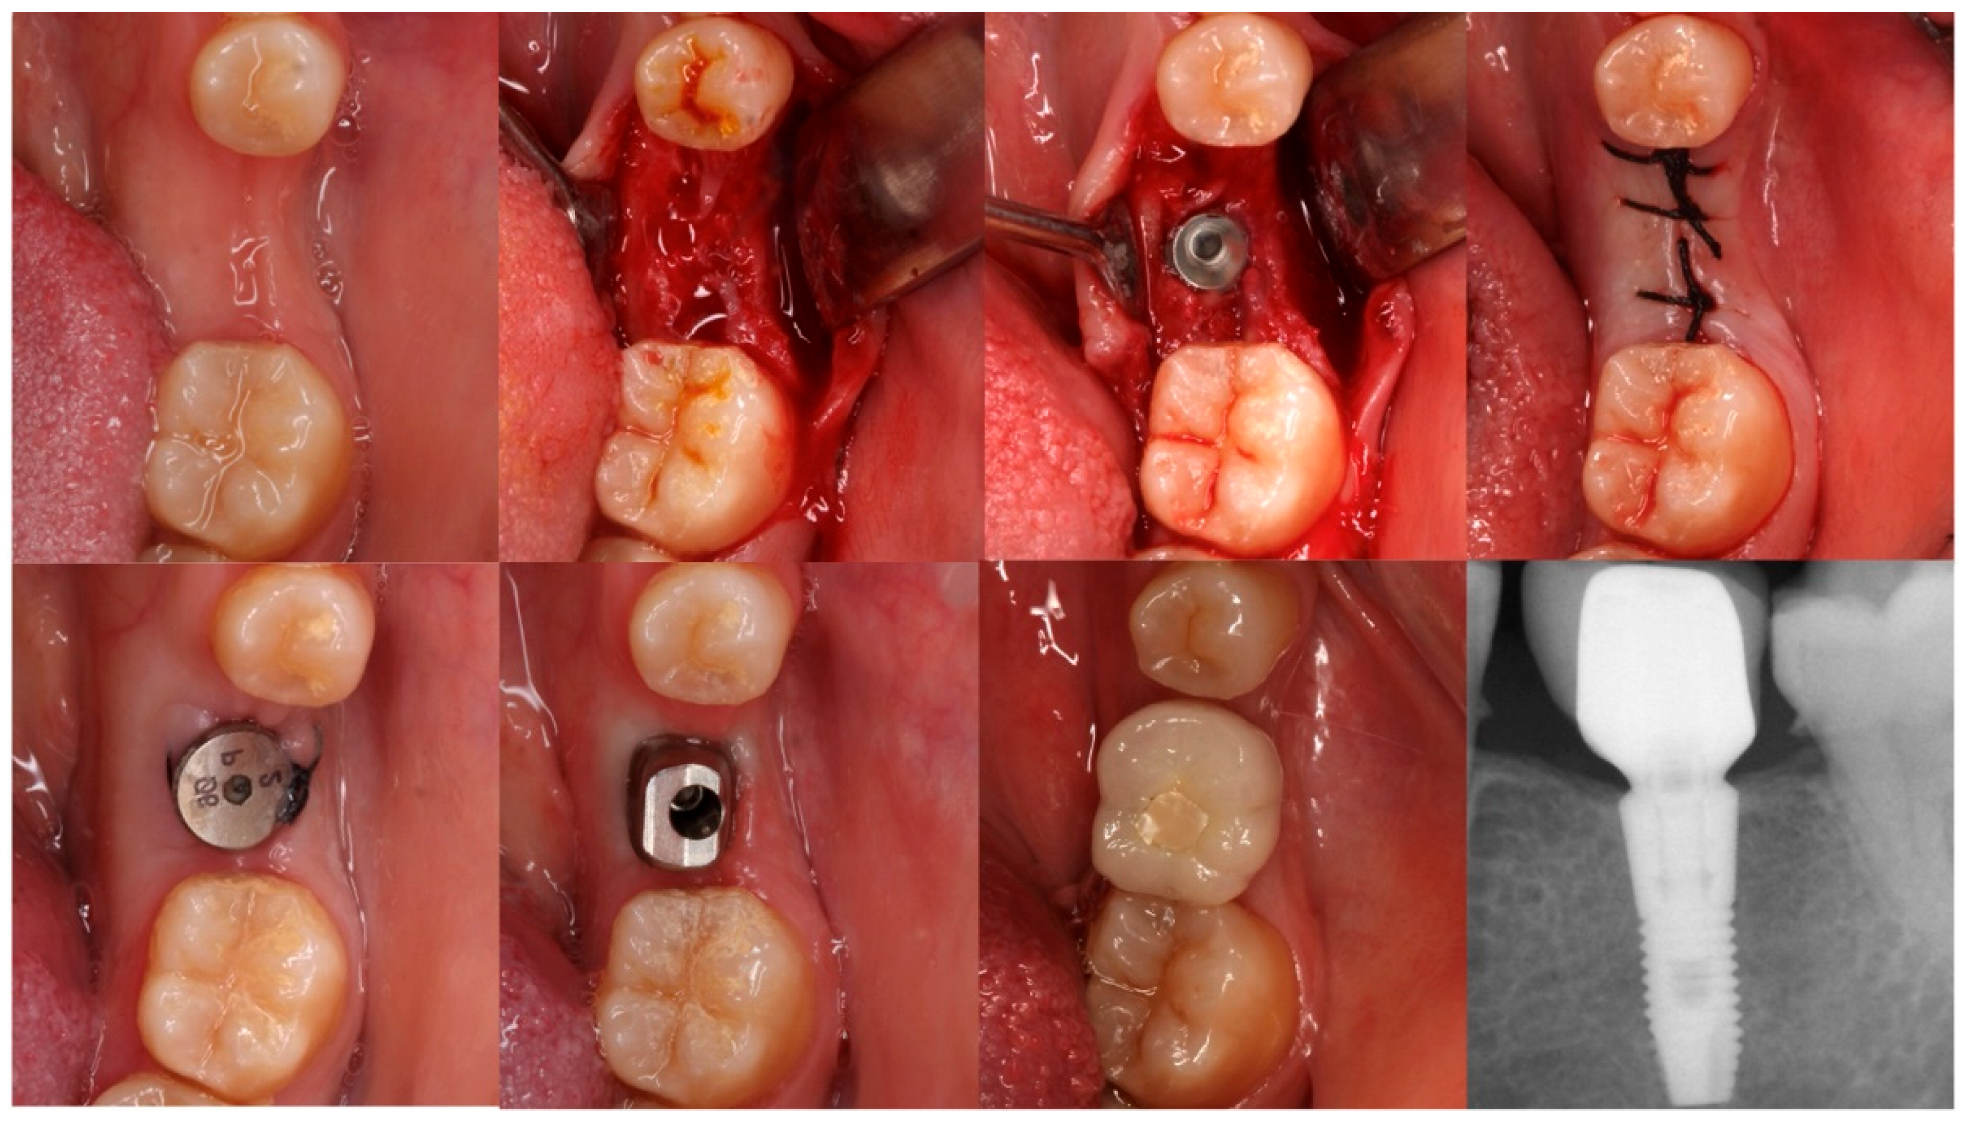

2.4. Clinical Procedure